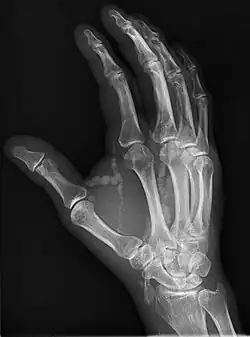

Die Ausscheidung von Calcium ist vermindert, im Blutserum finden sich erhöhte Cholecalciferolwerte bei normalen Calciumwerten. Eine Hyperphosphatämie kann, muss aber nicht vorliegen.[2][5] Der Nachweis der Verkalkungen kann bildgebend erfolgen, am deutlichsten auf dem Röntgenbild.[6]